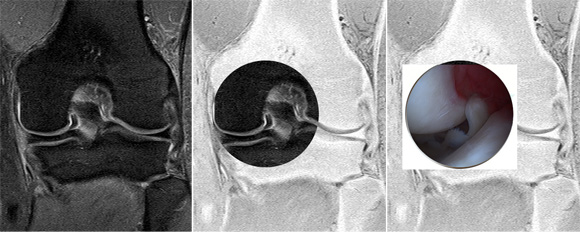

L'objectif principal de cette étude était de présenter une synthèse de la littérature actuelle afin de fournir un outil utile pour des cliniciens dans l'analyse radiologique du ménisque. L’imagerie par résonance magnétique (IRM) est la méthode la plus précise et la moins  invasive pour le diagnostic des lésions méniscales. Cette technique a révolutionné l’imagerie du genou et est devenu le « gold standard » de l’imagerie du ménisque. Elle permet de confirmer et de caractériser la lésion méniscale, son type, son extension, son association éventuelle à un kyste, l’extrusion méniscale,  l’évaluation du cartilage et de l’os sous-chondral.  Toutes les descriptions anatomiques ont été clairement illustrés dans cet article  par des images IRM,  arthroscopique et / ou dessins.  Nous avons également décrit  la radiographie standard  pour les diagnostiques différentiels comme l’arthrose. L'échographie est rarement utilisé comme un outil de diagnostic pour les pathologies méniscales. L’arthroscanner avec reconstructions multiplanaires peut détecter certaines fissures méniscal non visible à l'IRM. L’arthroscanner est également utile en cas de contre-IRM, dans l'évaluation post-opératoire de sutures méniscales ou pour l’analyse  du cartilage recouvrant les surfaces articulaires.

Traitement de la languette méniscale: image arthroscopique

La régularisation de la languette du ménisque est réalisée sous arthroscopie. Cette régularisation est faite à l’aide de petits instruments.